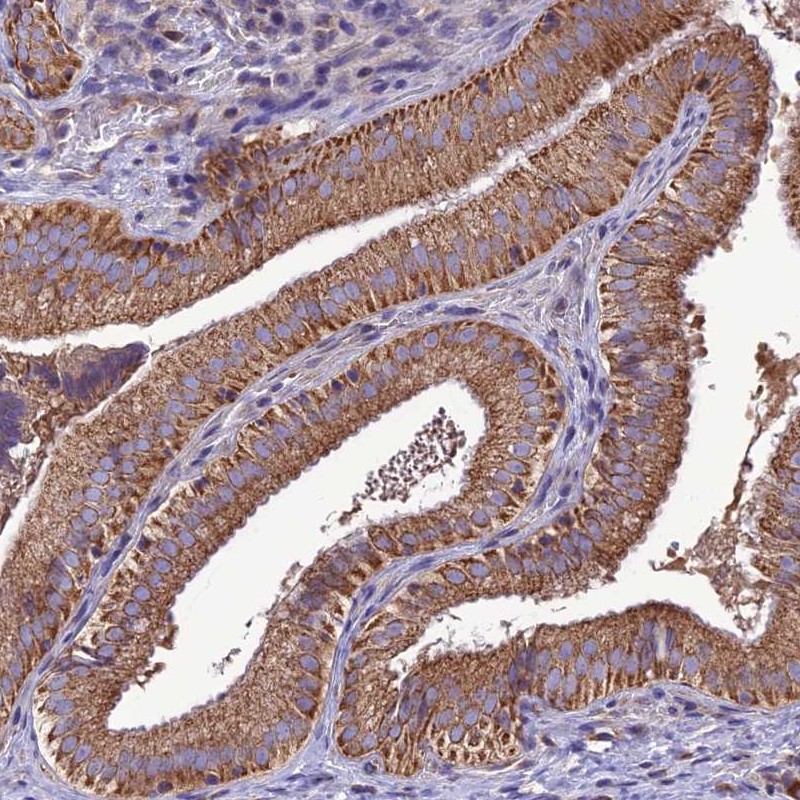

Immunohistochemical staining of human gallbladder shows strong cytoplasmic positivity in glandular cells.